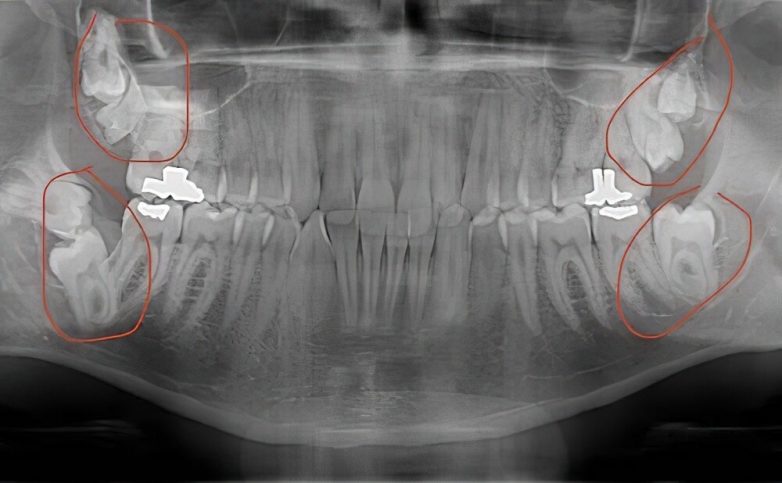

4. У человека было семь зубов мудрости. Ему их удалили. У большинства людей четыре зуба мудрости, по одному в каждом углу